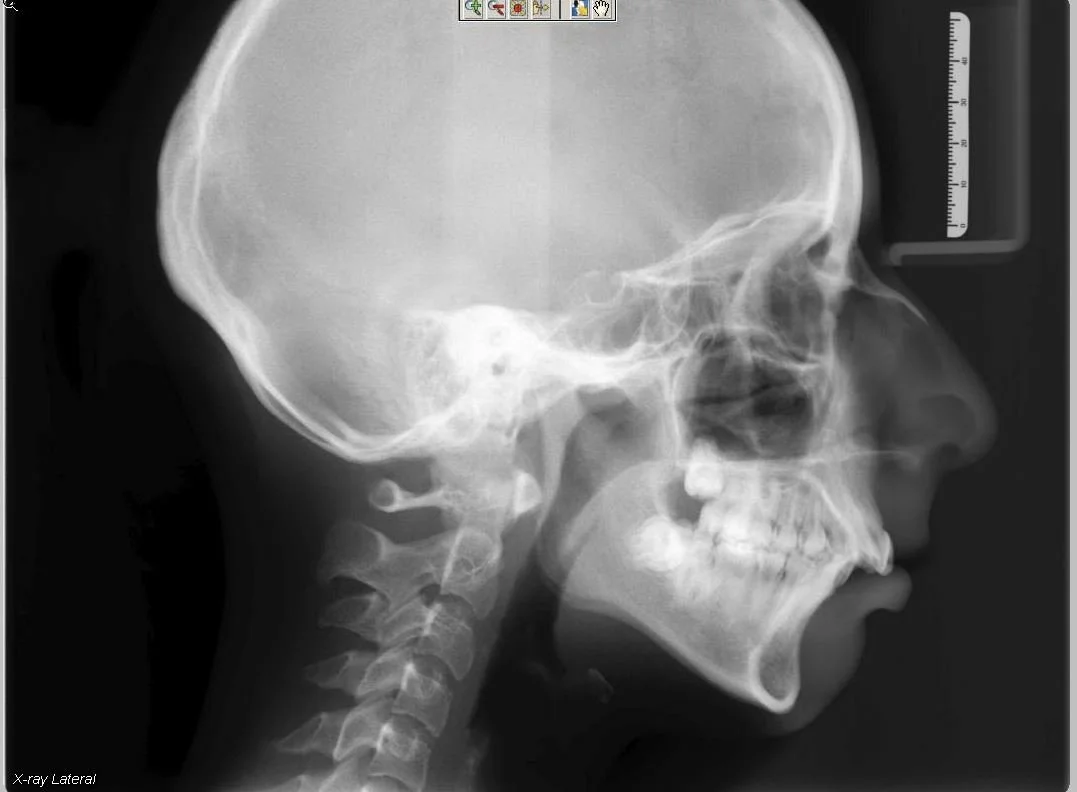

5.JPG